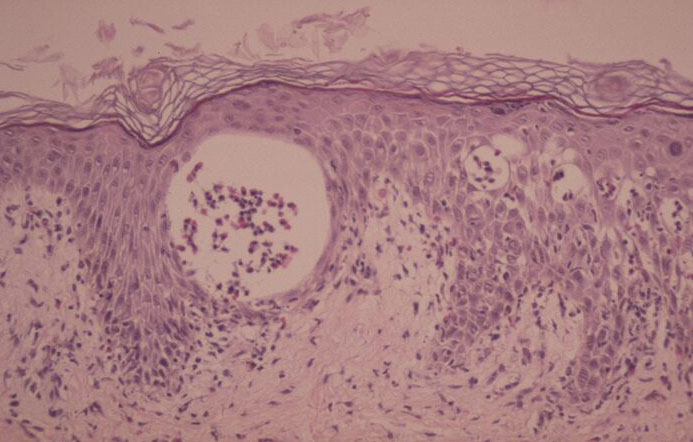

The vesicles seen during the first stage arise within the epidermis and are associated with spongiosis. They are of the type seen in dermatitis . However, they differ from the vesicles of dermatitis by the numerous eosinophils within them and around them in the epidermis (eosinophilic spongiosis) . The epidermis between the vesicles often shows single dyskeratotic cells and whorls of squamous cells with central keratinization. Like the epidermis, the dermis shows an infiltrate containing many eosinophils and some mononuclear cells.